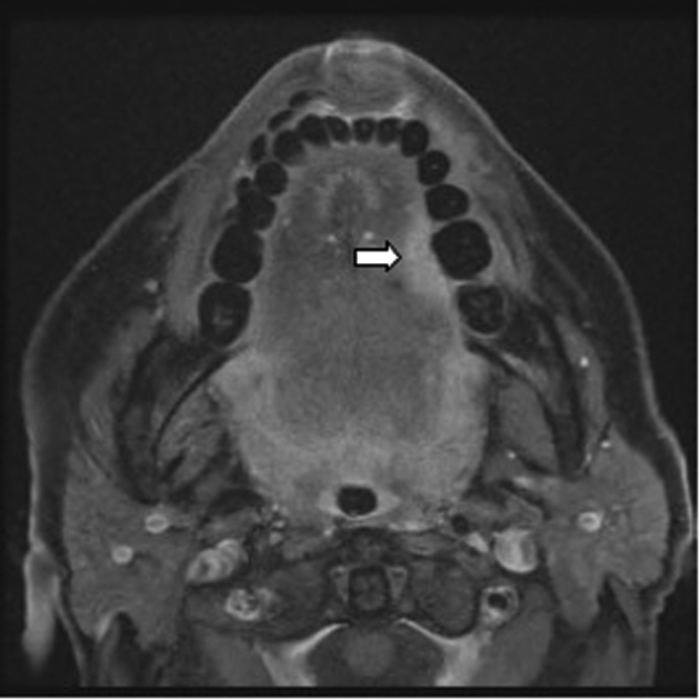

A 55-year-old female presented with a three week history of otalgia. Otoscopy was normal. Examination demonstrated an indurated erythematous mass on the left lateral border of the tongue, later confirmed as a squamous cell carcinoma.

The imaging modality of choice for the tongue is contrast enhanced MRI (Figure 6).

Figure 6: Post contrast T1W FAT SAT axial MRI demonstrating an enhancing

tumour on the left lateral border of tongue (white arrow).